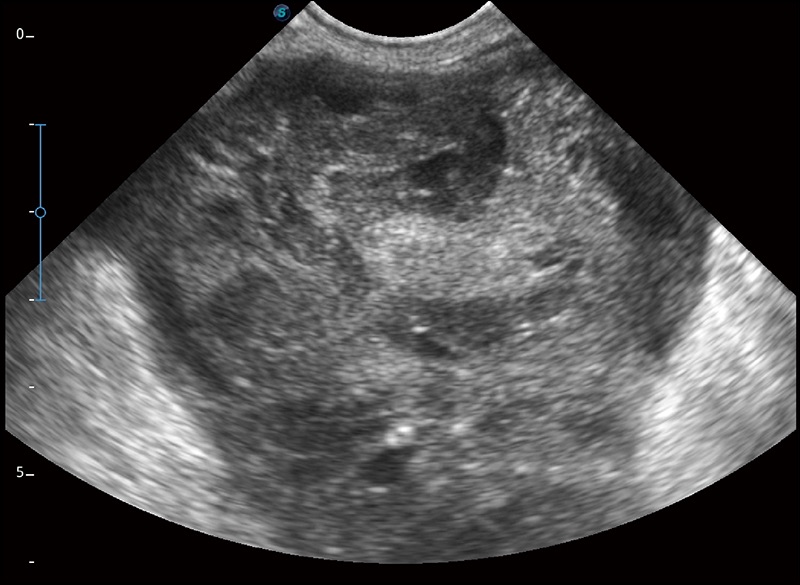

α1卓越的图像质量和便捷的工作流程,使每位宠物医生都能轻松扫查。其全面的兽用应用功能和紧凑型的结构设计,可以满足动物检查的多种需要。专业的预设检查模式和多领域测量软件包有助于为不同类型的动物提供检查, 让宠物医生能够出色的完成工作。

实时宽景成像

可实时观察感兴趣区域和病变位置